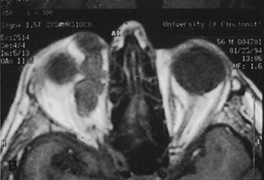

Magnetic resonance imaging is useful in selected cases, especially when evaluating the orbital cranial junction. Significant bony artifact and a lack of orbital fat in the orbital apex make CT scan resolution of the orbital apex structures poor. Because cortical bone has low signal on MRI, there is no bone artifact when viewing the orbital apex on MRI. The lack of intervening fat in the apex to provide contrast is overcome on MRI because contrast is provided by the individual nuclear characteristics of each tissue so that the orbital apex structures are visualized well. Consequently, conditions that affect the optic nerve and chiasm, such as optic nerve meningioma and glioma, generally are evaluated with MRI rather than CT scan (Fig. 2).

Fig. 2. A. Axial orbital CT scan of right optic nerve meningioma. Note lack of detail in orbital apex. B. Axial orbital MR image, same patient. Note increased detail in orbital apex owing to lack of bone artifact. C. MRI with gadolinium contrast. Note extension into brain not easily appreciated with CT scanning or MRI without contrast.